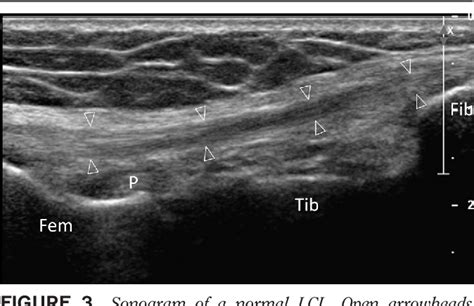

ECR 2015 / C-2071 / Chronic MCL syndrome: anatomy ...

ECR 2015 / C-2071 / Chronic MCL syndrome: anatomy ... from posterng.netkey.at